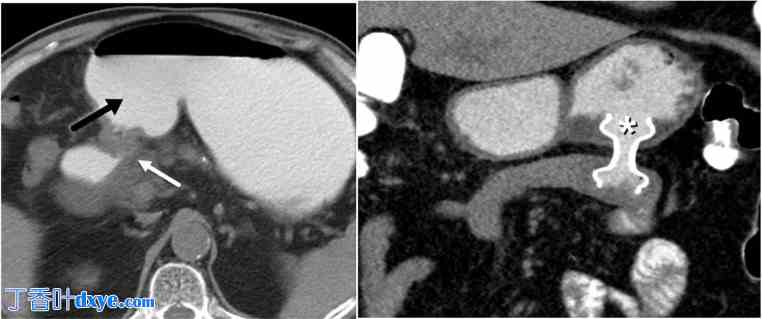

胆囊内 LAMS 的最佳留置时间尚未确定。除非胆囊管阻塞得到解决,否则从胆囊中移除 LAMS 通常会导致胆囊胃造口自发闭合和复发性胆囊炎。另一方面,如果支架无限期地留置,可能会发生支架移位或胆囊壁侵蚀性损伤以及胆囊/胃/十二指肠壁出血。据报道,长期放置支架(长达 3 年)没有发生与支架相关的不良事件。有传闻称植入时间更长,没有不良事件,例如作者已经证明的(图 3)。

图 3。

3.jpg

86 岁女性,因胆总管结石并发急性胆囊炎和上行性胆管炎而就诊。A. 增强轴向 CT 图像显示胆结石、胆囊壁增厚和急性胆囊炎胆囊周围积液(白色星号),并发胆总管结石引起的上行性胆管炎(白色箭头)。B. 增强轴向 CT 显示中度双叶肝内胆管扩张(黑色箭头)。C. 增强冠状 CT 图像显示 LAMS(白色箭头)将胆囊引流到十二指肠,并且在同一次 ERCP 过程中放置​​了胆道支架(黑色箭头),该患者不适合手术。胆道支架和 LAMS 均保留了 5 年。患者随后又发作了一次胆管炎,最终因无关原因去世,享年 92 岁